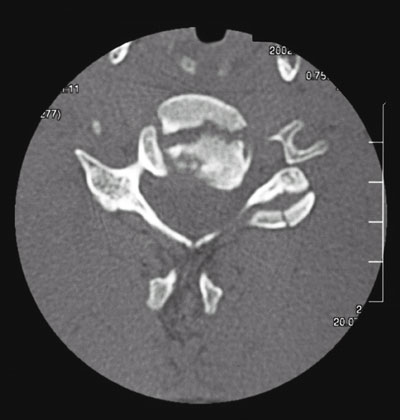

Abb. 1+2 von links

Instabiler Bruch des 5. Halswirbel-Körpers mit Abknickung der Hals-Wirbelsäule und Bruchspalt im Wirbelkörperhinterkantenbereich.

(links normale seitliche Röntgenaufnahme, rechts Schichtbild in der Computertomographie